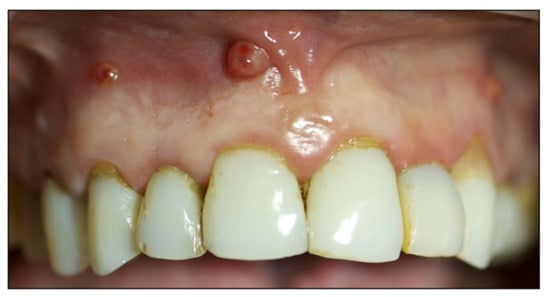

2. Case Report